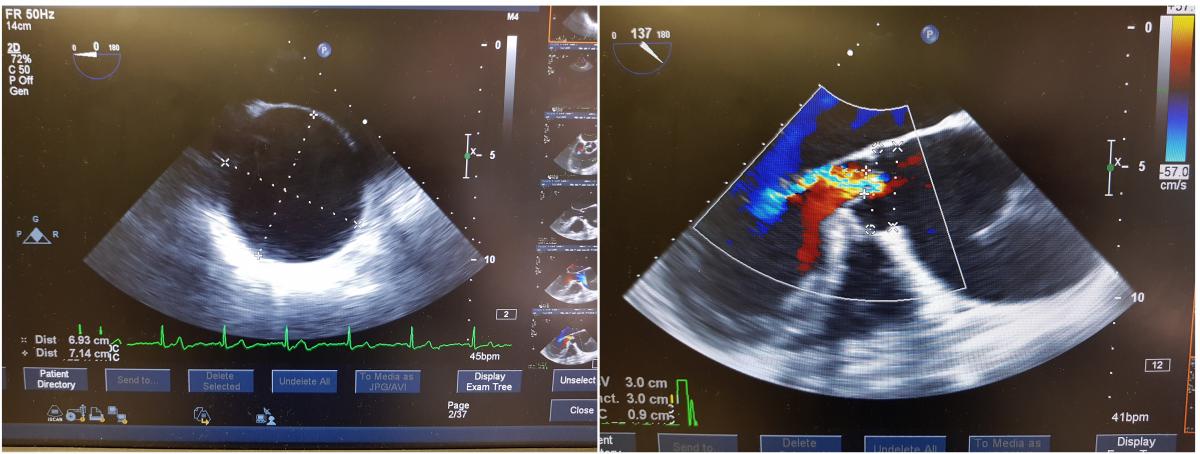

Perioperative TEE is shown in Figure 2. Figure 3 depicts the operative field before and after the ascending aorta replacement.